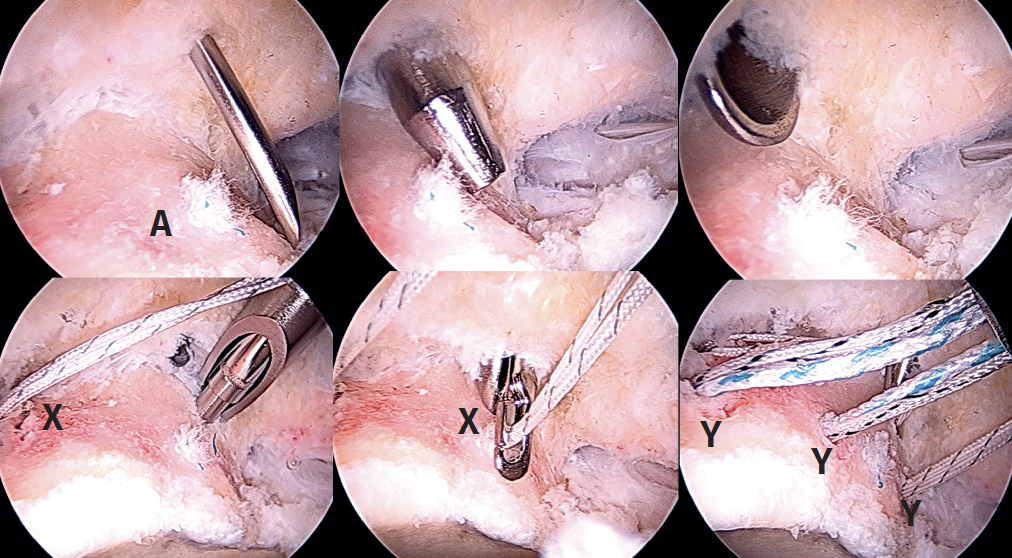

Preparation of the segmental acetabular reconstruction

For the treatment of the labrum we perform labral reconstruction with tibialis anterior allograft using the pull through technique(7) and tensionable technology, employing the posterolateral portal as accessory portal for positioning the graft. For this procedure, use is made of a tibialis anterior allograft that is prepared to obtain a diameter of 6-7 mm and a length of about 18 cm. Using FiberLoop® suture, the extremities are prepared with the SpeedWhip® (Arthrex) technique (Figure 5). Once the graft has been prepared, four 1.8 mm FiberTak® Knotless anchorings with tensionable technology (Arthrex) are implanted in the acetabular margin in the 11 to 3 o'clock position, distal to the previously mentioned anchorings, which we will refer to as second row anchorings, through the middle anterior portal or from the DALA, and then we retrieve the sutures of these anchorings through the DALA. During perforation and pre-drilling of the anchoring, the arthroscope is to be placed in a position allowing assessment of the joint cartilage, in order to make sure that the drill is not located between the subchondral bone and the surface of the joint cartilage. In order to prevent the anchorings from penetrating into the acetabular cartilage, the angle of the margin must be determined to ensure adequate placement. The successive filaments are placed in the field aligned and spread out in a fan-like manner from inferior-anterior to posterior-superior.

Introduction of the graft for labral reconstruction

Once all the sutures have been positioned, forceps are introduced from the posterolateral portal, taking care that they lie posterior to the last anchoring, with positioning within the joint. From the middle anterior portal we introduce the suture anchored to what will be the posterior part of the graft, likewise taking care that it lies anterior to the most anterior anchoring. This suture is retrieved from the posterolateral portal using the previously introduced forceps, applying traction to introduce the graft, and making it emerge through the posterolateral portal (Figure 6). At this point we fix the graft by passing sutures from the most anterior anchoring of the second row of anchorings, through the anterior part of the tibialis tendon, and it is then finally introduced and sutured. The sutures are then passed around the tendon graft in sequence, and are tightened little by little, maintaining traction from the posterolateral portal, and fixing and positioning the entire plasty from anterior to posterior (Figure 7). Once all these steps have been completed, the excess graft is radiofrequency amputated from the posterolateral portal.